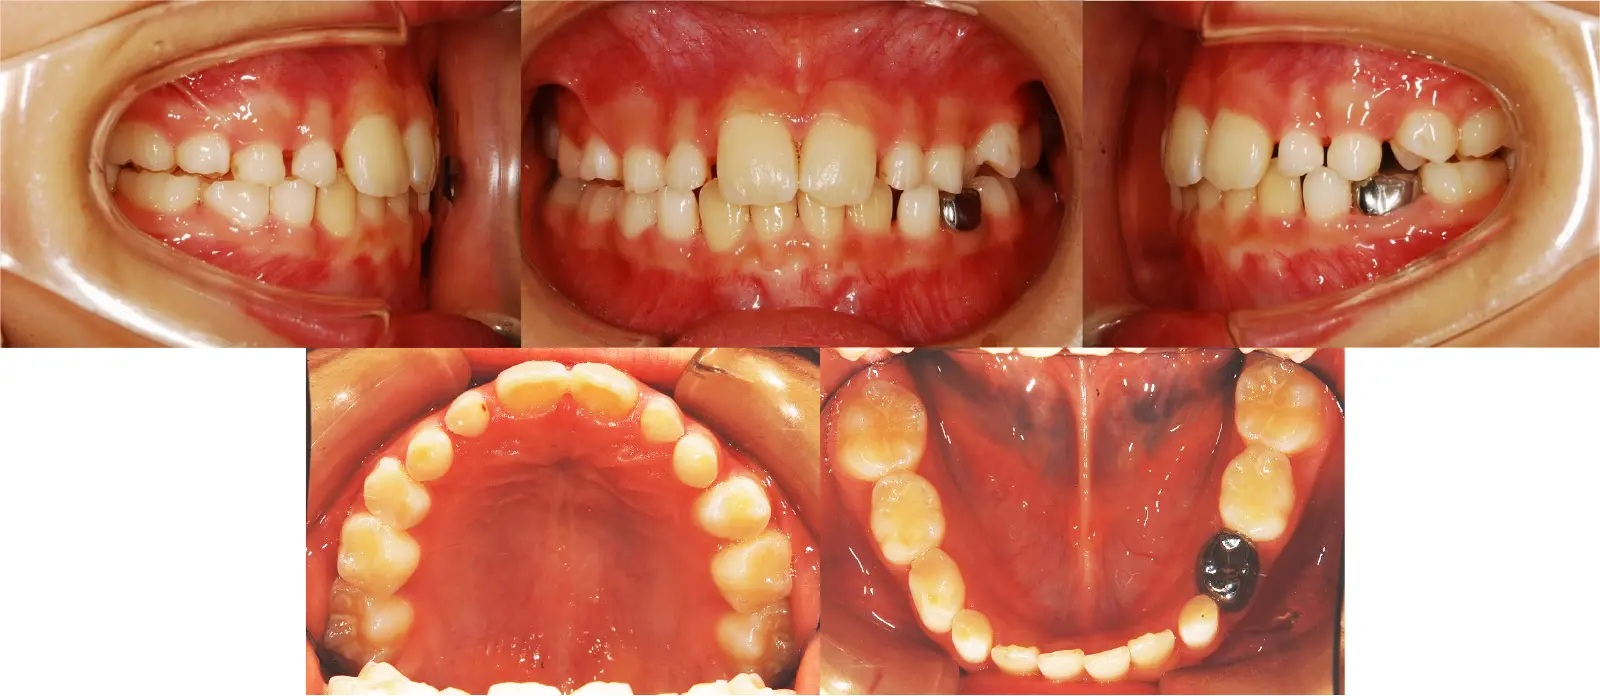

アングルⅡ級 軽度叢生を伴う下顎前突症

第一段階の治療のみで、

永久歯は問題なく萌出し、安定している

- 主訴

歯のガタガタと切端咬合

- 年齢

8歳

- 治療期間

1年3ヶ月

- 治療回数

7回

- 治療に用いた主な装置

2by4、フェイシャルマスク、拡大床

- 治療費

400,000円(税別)トータル料金

- 抜歯部位

非抜歯